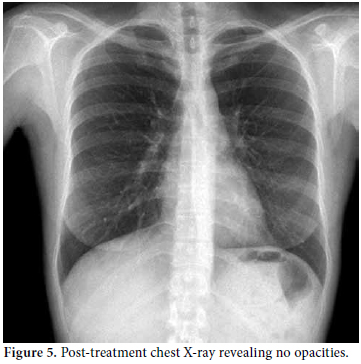

Consultations were then held with the pulmonary medicine and rheumatology departments regarding the eosinophilia identified in the CBC, pulmonary opacities revealed via chest X-ray, and the patient's past history of asthma (Figure 3). Furthermore, cranial computed tomography (CT) was performed on the day after the angiography which showed neurological involvement or paranasal sinus abnormality with a prediagnosis of CSS. The results of the cranial CT were also consistent with chronic sinusitis. The presence of asthma, hypereosinophilia of >10%, chronic sinusitis, and pulmonary opacities represent four of the six ACR criteria required for the diagnosis of CCS.[5] Our patient tested negative for anti-nuclear antibodies (ANAs), anti-double stranded DNA (antidsDNA), extractable nuclear antigens (ENAs) and anti-neutrophil cytoplasmic antibodies (ANCAs). The corticosteroid methylprednisolone at an initial dosage of 80 mg per day (1 mg/kg/d) was prescribed after the termination of the tirofiban infusion. Afterwards, the patient's eosinophil levels in the CBC decreased to normal ranges, and symptomatic relief was completely provided. Control coronary angiography was performed one week later, and the thrombotic lesions had disappeared (Figure 4). In addition, chest radiographs showed complete resolution of the opacities (Figure 5). After two more weeks, control echocardiography was performed revealing a normal morphology of the ventricles without any segmental wall motion abnormalities. Furthermore, the pericardial fluid had also disappeared.